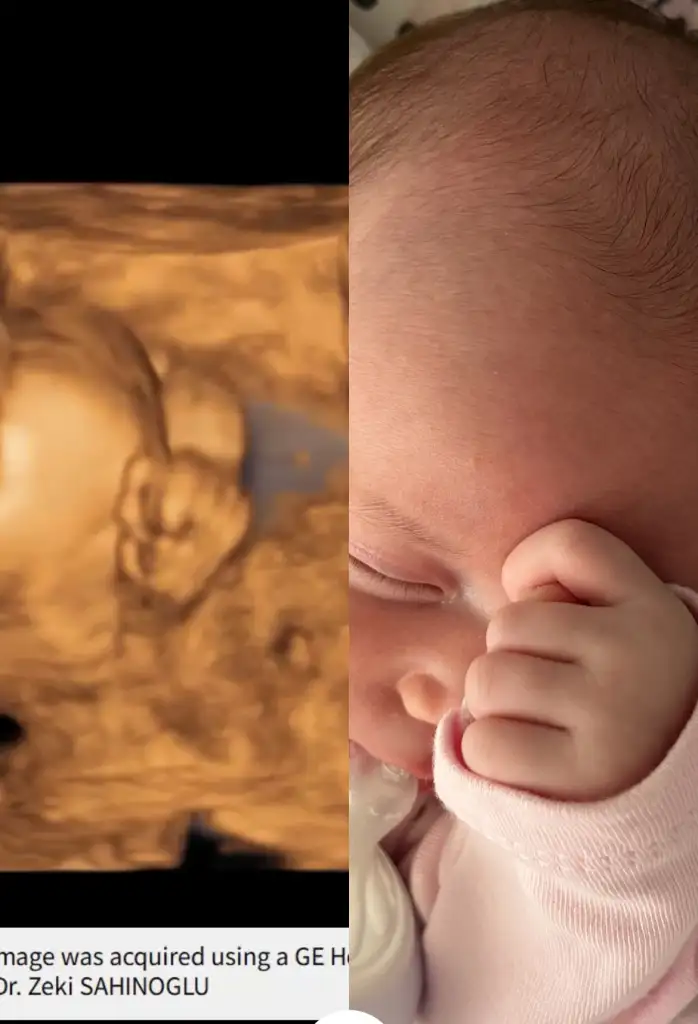

Ahahahahha yicemmm. Benimkinin de ultrason fotolarda eli hep yuzundeydi uyurken hala uyurken iki eli yanaklarinda